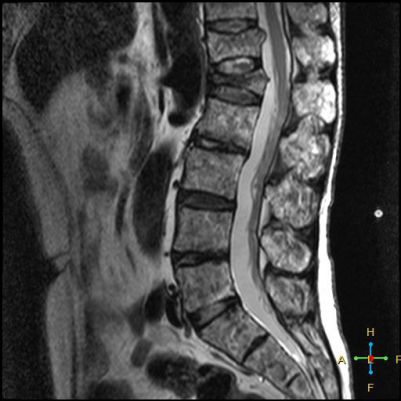

2 良性压缩性骨折 椎体形态:楔形、凹陷形。 椎体连续性病变(骨质疏松):新鲜、陈旧骨折并存。

椎间盘改变:椎间盘增厚呈双凸透镜状, 椎间盘疝入椎体, 形成许莫氏结节。

椎体后上角或后下角向后翘起, 呈尖突样突入椎管, 具有特异性,为其它原因的骨折所少见。

——良性压缩性骨折MR信号特点—— 良性骨折的修复过程:缺血性变化--修复(骨髓水肿、血流增加或充血现象)--修复近完成(血流恢复正常)--慢性期(脂肪组织再生)。 正常成人:椎体为黄骨髓,T1WI 、T2WI 均为高信号。 当骨髓内出现水肿时,T1 低信号, 与残余的正常骨髓形成明显对比,所以椎体压缩骨折后,MR 信号改变以 T1WI 上观察最好;而在常规 T2WI 图像上,病变骨髓的长 T2 高信号与正常骨髓脂肪信号差别较小,不易观察;T2WI 脂肪抑制技术对于突出显示骨折区长 T2 组织信号具有独特优势,对于判断椎体是否发生脂肪变及骨折是否愈合也有一定价值。 急性早期,椎体压缩,局部缺血,骨髓水肿,T1WI 不均匀低信号,T2WI 高信号,增强扫描无明显的强化。 随后,骨折部位开始修复,血流量增加,增强扫描可出现明显的强化,平扫信号无改变。 慢性期,骨髓内脂肪组织再生,T1WI 椎体内呈混杂高信号。

由于大多数外力轻微,椎体内多形成范围局限、移位不明显的骨折线,骨折线周围水肿亦多局限,因此,较少出现全椎体信号异常。

椎体后角回避现象:T1WI 椎体上部或大部呈低信号, 而后角信号不变。